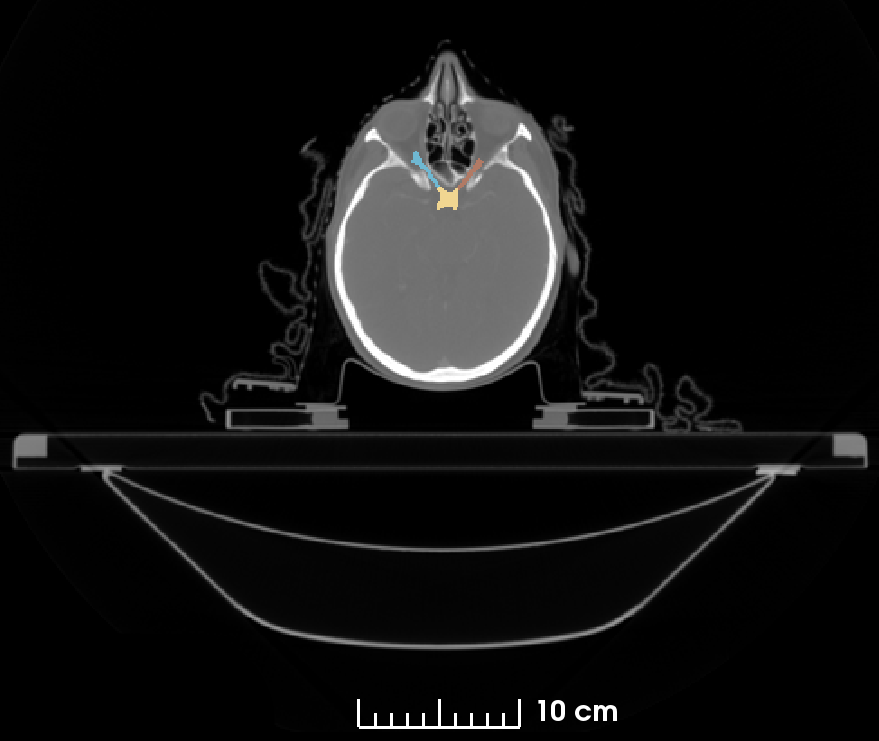

Figure 1: Average background and organ volume imbalance ratios of seven HAN organs (from left to right: Background, Brainstem, Optic Chiasm, Optic Nerve left/right, Parotid Gland left/right, Mandible) for four different patch-size sampling strategies, evaluated over one training epoch.

3.3 Class Imbalance Measurement

As the currently most advanced general purpose approach for medical image segmentation we mainly follow the 3D nnU-Net framework, but adapt the loss function and also the patch-size based on our class imbalance measurement as the parameters directly influencing the class imbalance while training. Figure 1 shows the average imbalance of the organ and background volume ratios of the dataset within a training epoch for different training strategies. For the ratio measurement the dataset is rescaled following the spacing definition of the nnU-Net. Although the histograms visually show the difference of the organ volume ratios for the presented patch-size strategies, we propose to use the standard deviation σ𝜎\sigma of the class ratios as a single measurement for the class imbalance. The standard deviation of the averaged in-patch organ ratios is a single and easily interpretable value. The ratios sum up to one, accordingly the standard deviation is the average distance to an ideally uniform distribution of in-patch organ ratios. Utilizing σ𝜎\sigma as a cost function with the patch-size as parameter allows us to find the training parameter with a minimal imbalance for the given dataset.

The nnU-Net as a general purpose segmentation framework is based on a fixed and a dataset dependent set of parameters. The patch-size defining rule of the network is based on the assumption that large windows have a more global context and hence improve the segmentation result. However, using the standard deviation σ𝜎\sigma of the organ volume ratios as a cost function to optimize the class imbalance within the patches, results in smaller patch-sizes than the global context maximizing patch-size assumption of the nnU-Net. Our measurement of the class ratio standard deviation σ𝜎\sigma naturally shows that the class imbalance is maximal (σ=0.3301𝜎0.3301\sigma=0.3301) if a whole image approach is used and minimal if the patch-size is minimal (σ=0.27146𝜎0.27146\sigma=0.27146 for a patch-size of 8×8×88888\times 8\times 8). Figure 1 shows the organ volume ratios, including the background of the sampling process using four different patch-sizes.

Reducing the patch-size directly influences the class imbalance within the sampled patches. The standard deviation, introduced as a measurement for the volume ratio imbalance within a training image patch, changes from σ=0.32605𝜎0.32605\sigma=0.32605 to σ=0.32337𝜎0.32337\sigma=0.32337 using the GPU memory optimized large patch-size of 192×160×5619216056192\times 160\times 56 compared to the suggested class imbalance optimized small patch-size of 96×80×4896804896\times 80\times 48. As visible in Figure 1, especially the ratio of the smaller classes increases within a patch. The improvement of the class imbalance therefore reduces the bias towards the large classes during the training and effectively results in an increase in performance of 2% in terms of the DSC and a significant increase of 2% regarding SD compared to the baseline nnU-Net framework. The 95HD is significantly reduced by 0.91 mm, yielding an improvement of 22% compared the baseline.